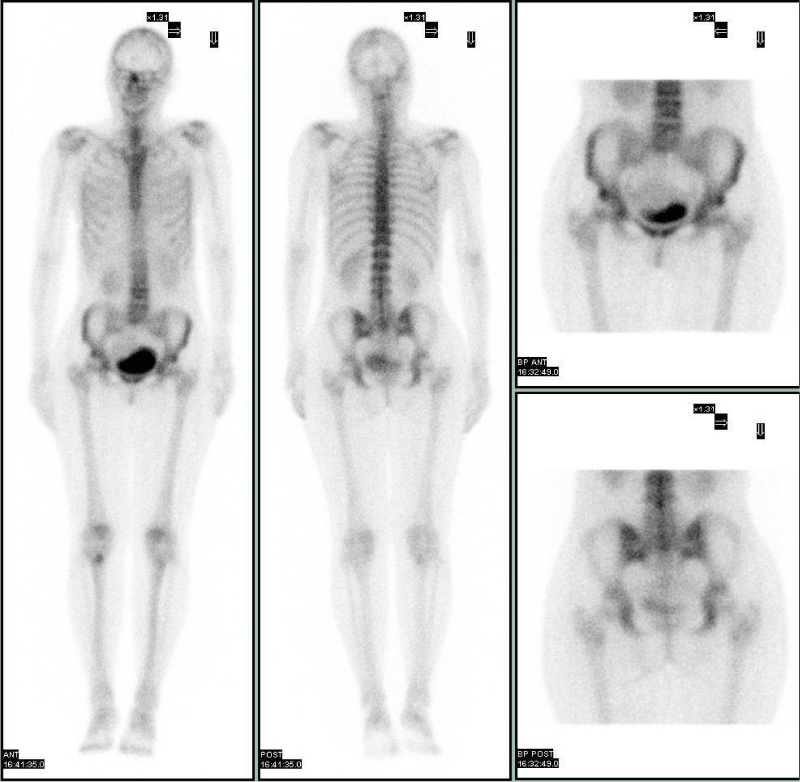

Case 1: Uterine fibroid on 99mTc-HDP bone scan

In this case we report a 66 aged woman with diagnosis of breast cancer came to our center for the staging of the disease. Therefore, a 99mTc-byphosphonates bone scintigraphy have been performed in order to focus on eventual secondary lesions. Concerning the main clinical request, the bone scan whole body image, obtained 2 hours after the i.v. injection of the osteotropic radiopharmaceutical, did not show any pathologic uptake of the tracer in the skeleton. Conversely, focusing on the pelvis region, it was evident an area with very faint fixation able to distort the profile and the shape of the full urinary bladder (Figure 1). Moreover, this incidental finding determined an ab extrinseco compression on the superior wall of the bladder. The detailed spot view, obtained after urination, confirmed the profile alteration of the bladder on the superior right side. The woman had no previous significant issues in gynecologic past and recent anamnesis and, moreover, the absence of reported clinical symptoms related to gynecologic disease didn’t induce the suspect of an altered gynecologic condition. This incidental finding required further investigations to assess their clinical relevance, therefore it was suggested a complementary morpho-structural examination by pelvic transvaginal ultrasound. She underwent both ultrasound and further morpho-structural exam (MRI) brought out a notable mass in the context of uterine wall that was reported as a uterine fibroid or leiomyoma.